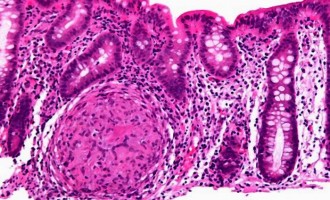

Την Τρίτη 16 Ιουνίου γινόμαστε μέρος της αλυσίδας προσφοράς του Allwyn Care – Πάμε στο Δημοτικό Θέατρο Πειραιά και γινόμαστε εθελοντές αιμοδότες και δότες μυελού των οστών Καρκίνος παγκρέατος: Μεγάλες ελπίδες από νέο φάρμακο που διπλασίασε το χρόνο επιβίωσης ασθενών

Καρκίνος παγκρέατος: Μεγάλες ελπίδες από νέο φάρμακο που διπλασίασε το χρόνο επιβίωσης ασθενών Eνέσιμο φάρμακο κατά του καρκίνου εξαφάνισε ολόκληρους όγκους σε ασθενείς

Την Τρίτη 16 Ιουνίου γινόμαστε μέρος της αλυσίδας προσφοράς του Allwyn Care – Πάμε στο Δημοτικό Θέατρο Πειραιά και γινόμαστε εθελοντές αιμοδότες και δότες μυελού των οστών Καρκίνος παγκρέατος: Μεγάλες ελπίδες από νέο φάρμακο που διπλασίασε το χρόνο επιβίωσης ασθενών

Καρκίνος παγκρέατος: Μεγάλες ελπίδες από νέο φάρμακο που διπλασίασε το χρόνο επιβίωσης ασθενών Eνέσιμο φάρμακο κατά του καρκίνου εξαφάνισε ολόκληρους όγκους σε ασθενείς